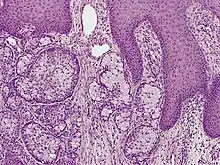

Eccrine carcinoma is a rare skin condition characterized by a plaque or nodule on the scalp, trunk, or extremities.[1]:669 It originates from the eccrine sweat glands of the skin, accounting for less than 0.01% of diagnosed cutaneous malignancies.[2] Eccrine carcinoma tumors are locally aggressive, with a high rate of recurrence. Lack of reliable immunohistochemical markers and similarity to other common tumors has made identification of eccrine carcinoma difficult.[2]

A skin biopsy is the most common test used to diagnose eccrine carcinoma.[2] The biopsy will detect growth of new or abnormal tissue. Another test that can be performed is using immunohistochemistry, but it is inconsistent.[2] Markers used to detect eccrine carcinoma consist of carcinoembryonic antigen, progesterone receptors, estrogen receptors, epithelial membrane antigen, pancytokeratins, and cytokeratin 7.[5][6]